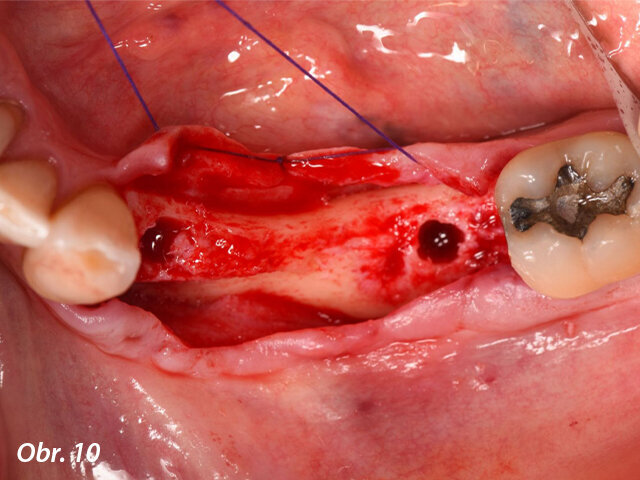

Meziodistálně byl implantát umístěn nejméně 1,5 mm od sousedního přirozeného zubu a mezi dvěma implantáty byla zachována vzdálenost 3,0 mm. Lůžka implantátů byla preparována podle pokynů výrobce a každý vrtáček byl použit za hojné irigace. Za účelem správné prostorové pozice implantátů byly použity paralelizační piny (obr. 8–10).